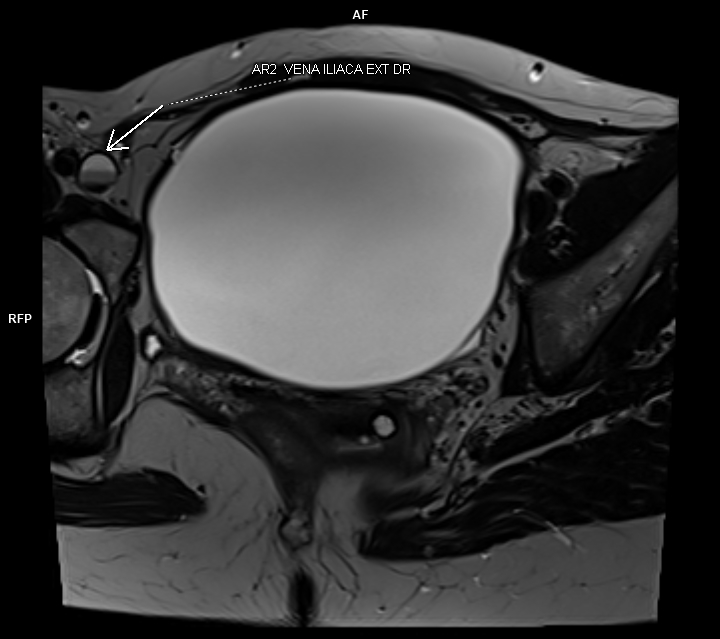

Figura 2: oblic-axial T2

Discuţie caz nr 100: Leziune expansivă voluminoasă este evidențiată la nivel pelvin cu apartenența ovariană dreapta. Formațiunea nu prezintă restricție de difuzie a apei, are conținut cu semnal lichidian, fără priză de contrast și perete subțire cu priză de contrast. Leziunea  nu conține porțiuni tisulare și nici septuri, amprentează dinspre superior vezica urinară și produce compresia venelor iliace cu un aspect tristratificat venos în amonte (vezi figurile 1 și 2). Pacienta a fost operată și diagnosticul a fost de chistadenom.